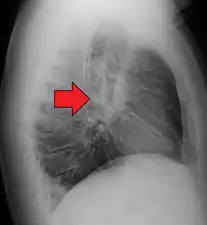

Chest X-ray showing the typical nodularity of sarcoidosis, predominantly in the hila of the lungs.

Chest radiograph changes are divided into four stages:[105]

1. bihilar lymphadenopathy

2. bihilar lymphadenopathy and reticulonodular infiltrates

3. bilateral pulmonary infiltrates

4. fibrocystic sarcoidosis typically with upward hilar retraction, cystic and bullous changes

Although people with stage 1 radiographs tend to have the acute or subacute, reversible form of the disease, those with stages 2 and 3 often have the chronic, progressive disease; these patterns do not represent consecutive "stages" of sarcoidosis. Thus, except for epidemiologic purposes, this categorization is mostly of historic interest.[28]